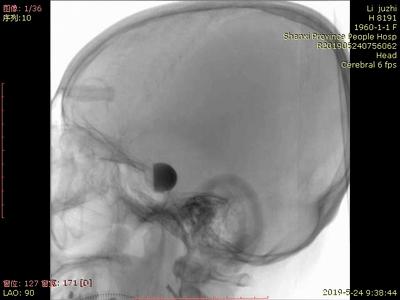

患者于入院前1天无明显诱因突发头。外院头颅CTA示:颅内动脉瘤。我院行DSA示:左侧大脑中动脉动脉瘤。

手术过程:

全脑血管造影可见左侧大脑中动脉动脉瘤,瘤体最大径:16.7mm,瘤颈宽:8.3mm。